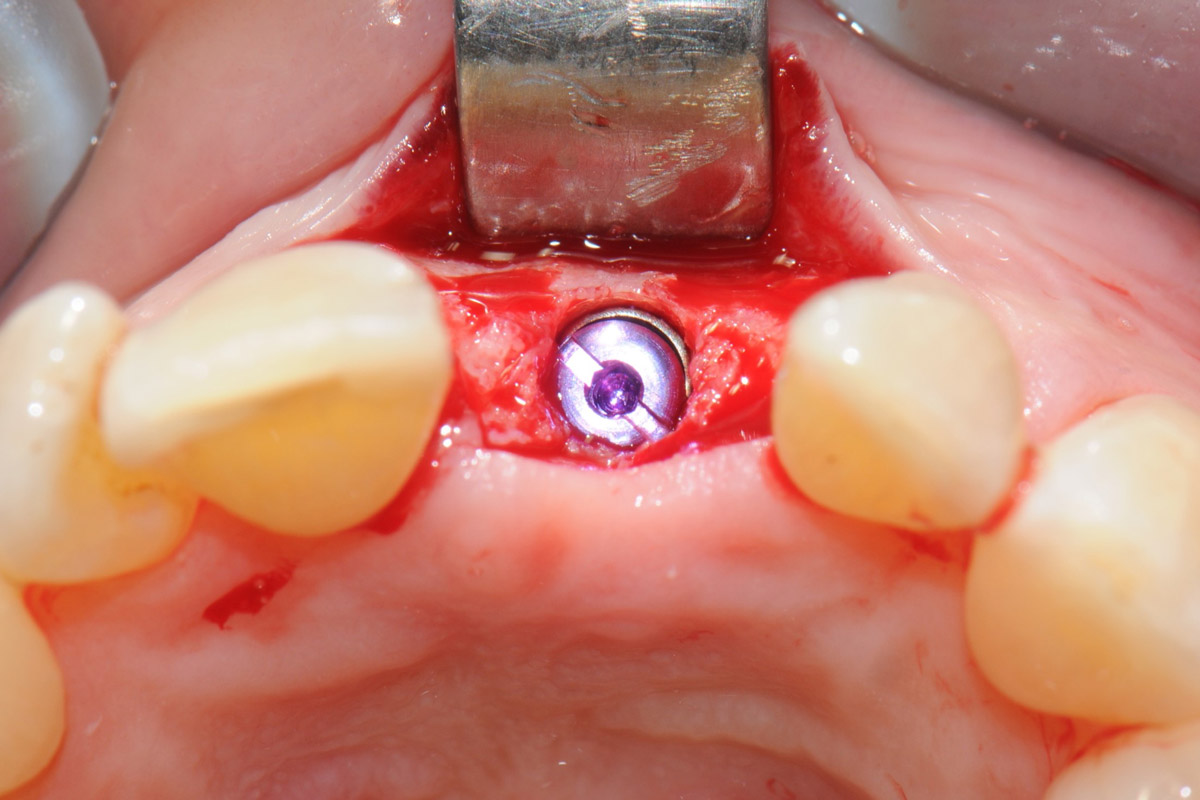

16/18 - Implant placementTooth extraction and socket sealing with mucoderm® - Dr. A. Rossi